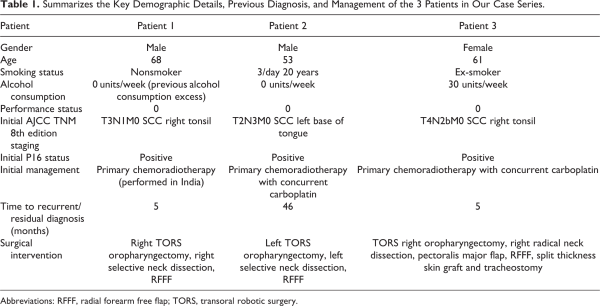

Patient 3 is a 63-year-old woman who was treated with induction chemotherapy followed by radical chemoradiotherapy for a T4N2bM0 tonsillar SCC. 4 months posttreatment a PET CT scan revealed metabolically active lesions within the right tonsil, glossotonsillar sulcus, and several right-sided neck lymph nodes. Patient demographic data is summarized in Table 1 and preoperative imaging is displayed in Figure 1.

Figure 1

Summary of patient preoperative imaging. TOP (Patient 1). Left-axial view contrast enhanced CT showing lesion within right tonsil suggestive of residual disease (red box). Right-axial PET CT showing a strongly FDG avidity within the same tonsillar lesion. MIDDLE (Patient 2). T1 axial view MRI demonstrating a 2-cm mucosal irregularity with increased enhancement in the left tonsillar fossa (red box). BOTTOM (Patient 3). Left-axial view contrast enhanced CT showing malignant appearing changes in right tonsil and glossotonsillar sulcus and an enlarged abnormal right neck node (red box). Right-axial view PET CT showing intense FDG uptake within enlarged right neck lymph nodes. FDG indicates fluorodeoxyglucose; MRI, magnetic resonance imaging; PET-CT, positron emission tomography-computed tomography.